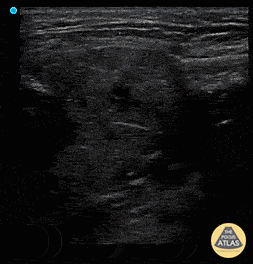

Soft Tissue - Sialadenitis

Patient has painless left sided facial swelling and no dental issues. See left submandibular gland swelling with ductal dilation and hyperechoic density in the far field representing sialolith and surrounding inflammation sialadenitis. Dr. Dustin Morrow